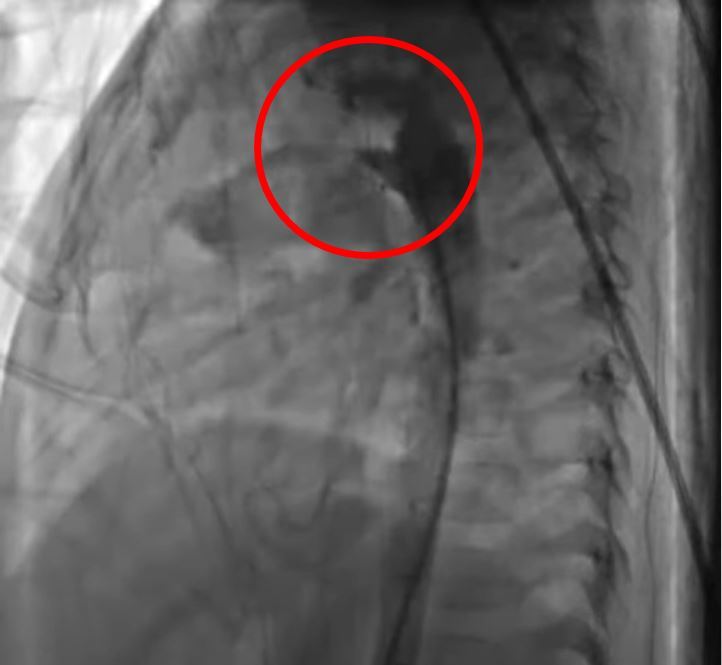

左圖:術前主動脈血液流入肺動脈。

「約90%的新生兒的動脈導管,在出生兩週內會進行閉鎖」裘品筠主任表示,嬰兒在媽媽體內時使用體循環,在主動脈與肺動脈之間相通的血管稱為動脈導管,一般在寶寶出生後二至三天會進行功能性閉鎖,開始了由肺部呼吸的肺循環,若未關閉,部份壓力較高的主動脈血液會流入肺動脈,加入肺循環而引起肺充血,稱為「開放性動脈導管」,發生率為1/2000,約佔先天性心臟病的10%。

圖說:主動脈與肺動脈之間相通的血管稱為動脈導管,一般在寶寶出生後二至三天會進行功能性閉鎖,開始了由肺部呼吸的肺循環,若未關閉,部份壓力較高的主動脈血液會流入肺動脈,加入肺循環而引起肺充血,稱為「開放性動脈導管」。